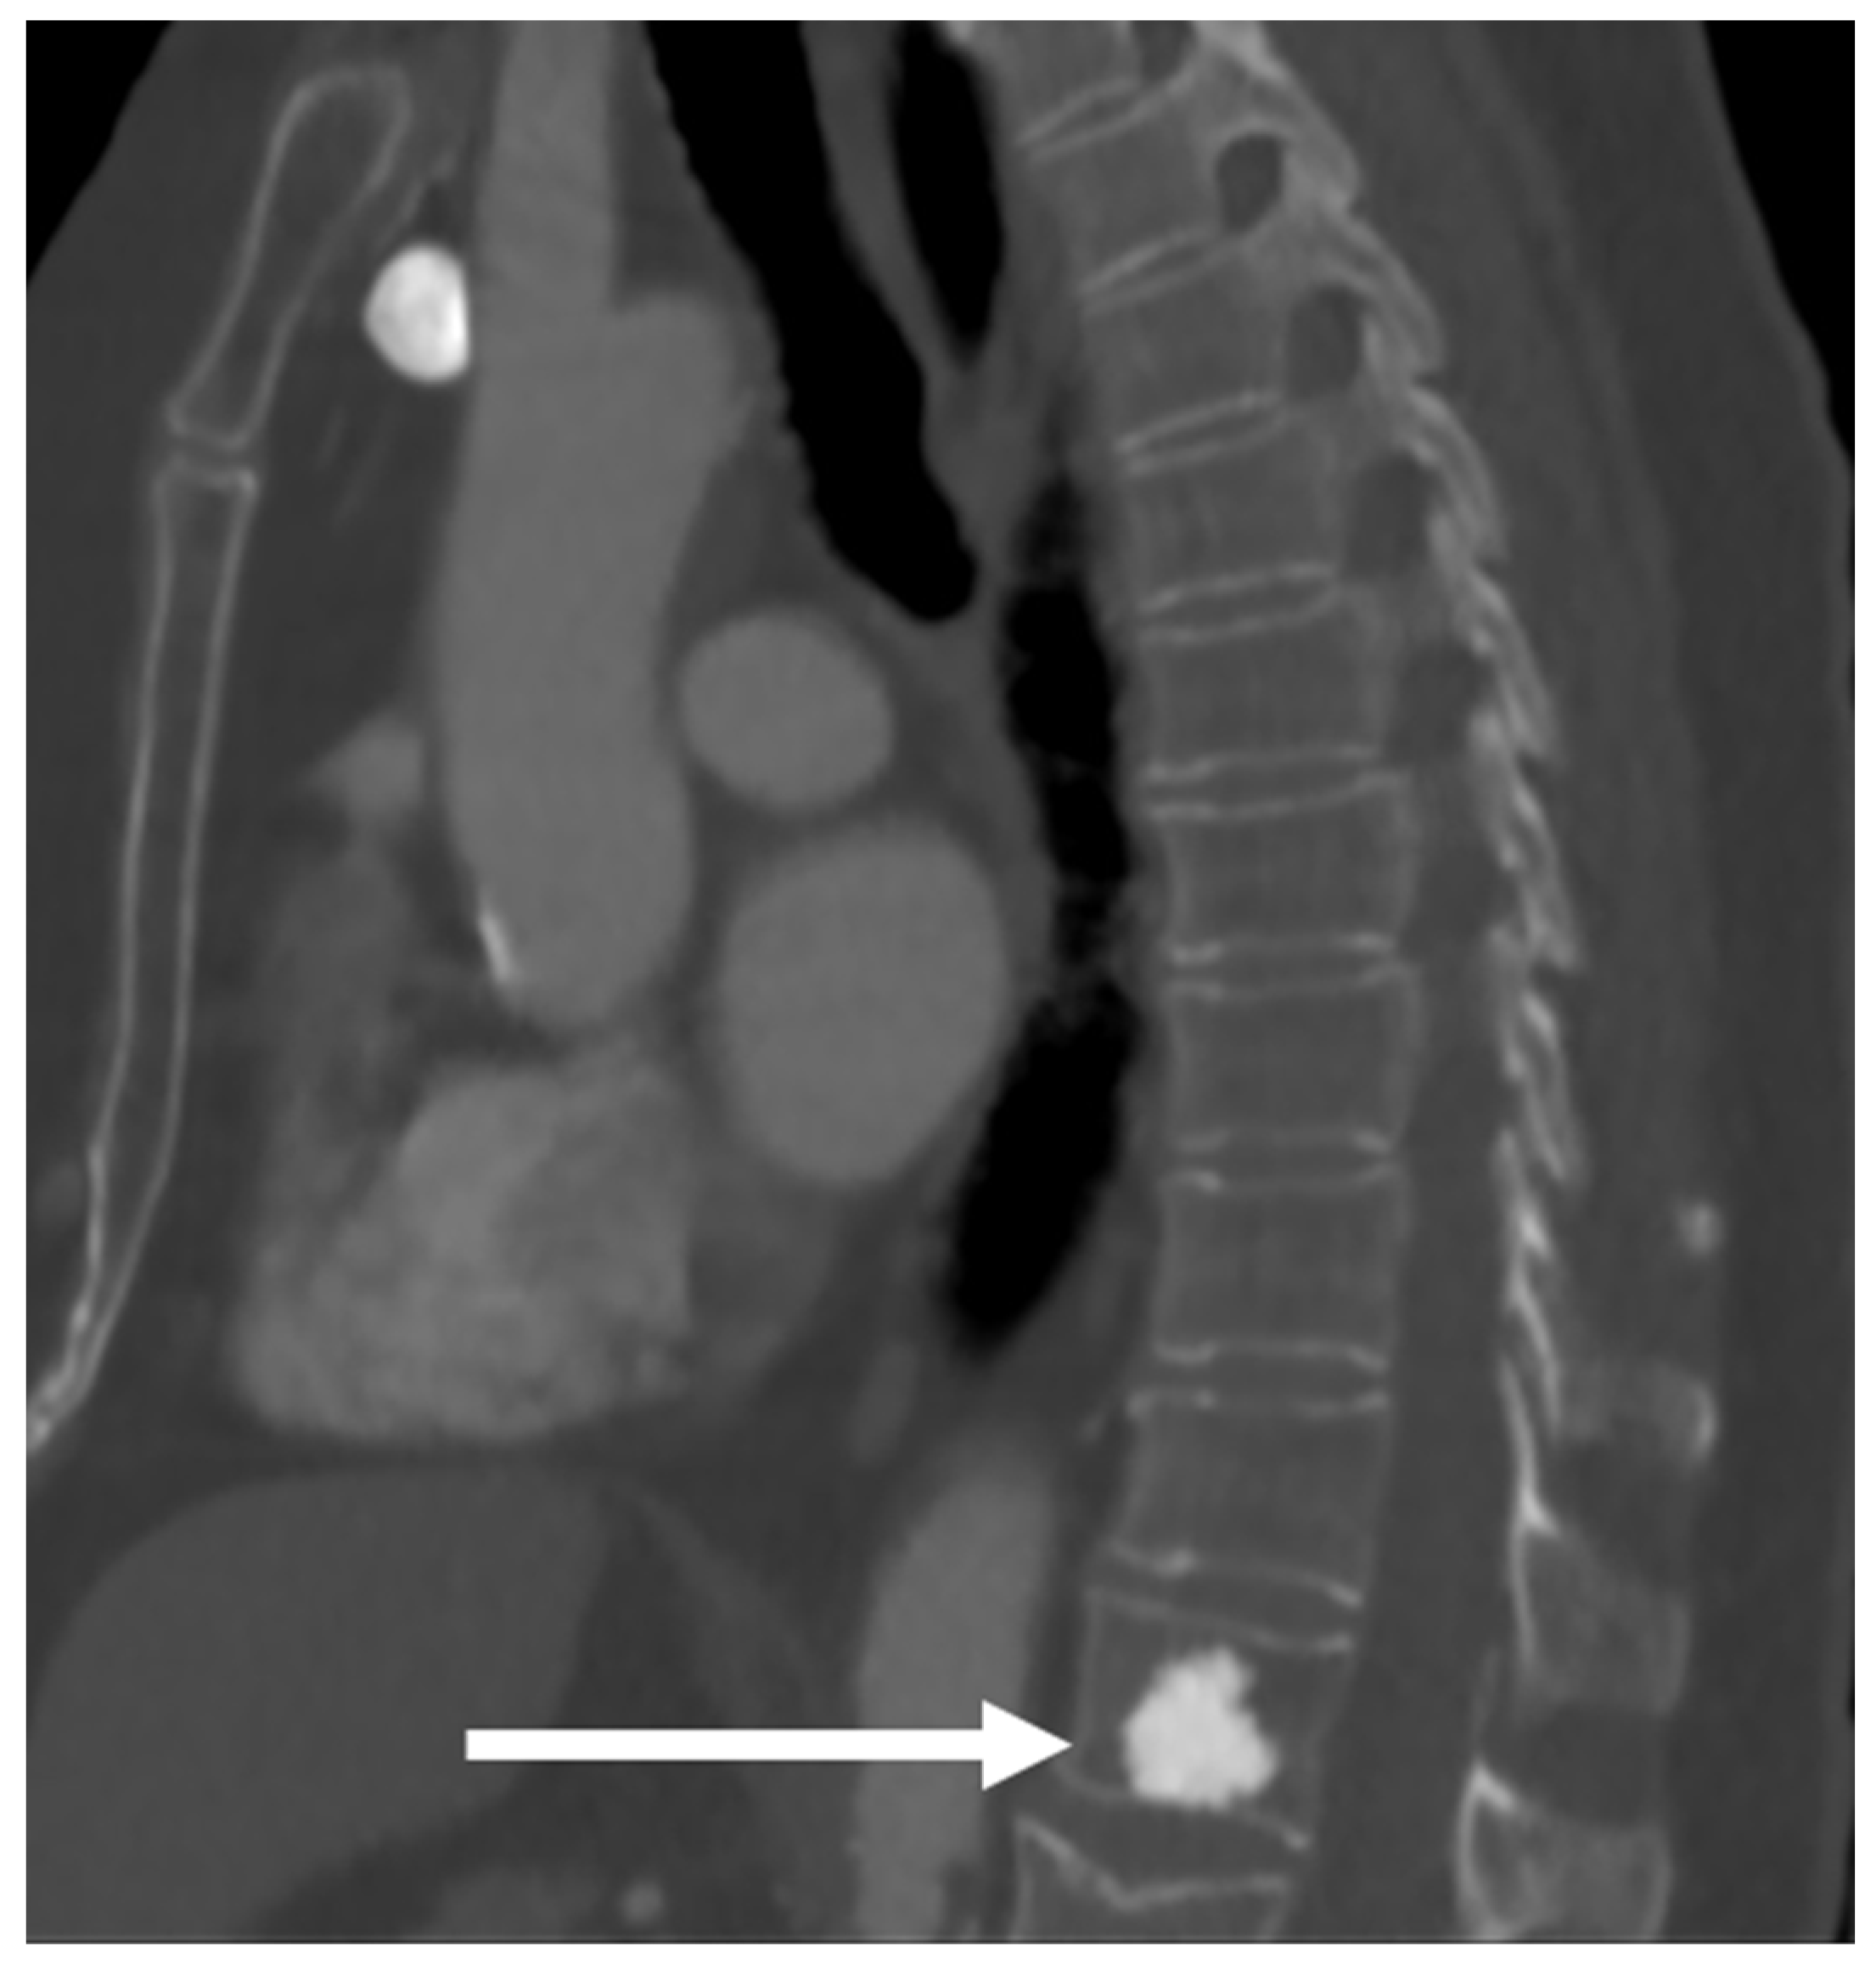

3.10. Notochordal Tumours

| Benign notochordal tumour | Midline lesion in the body. Sclerosis or trabecular thickening typically, but lysis can be present. | Low T1 and high T2 signal. No enhancement. |